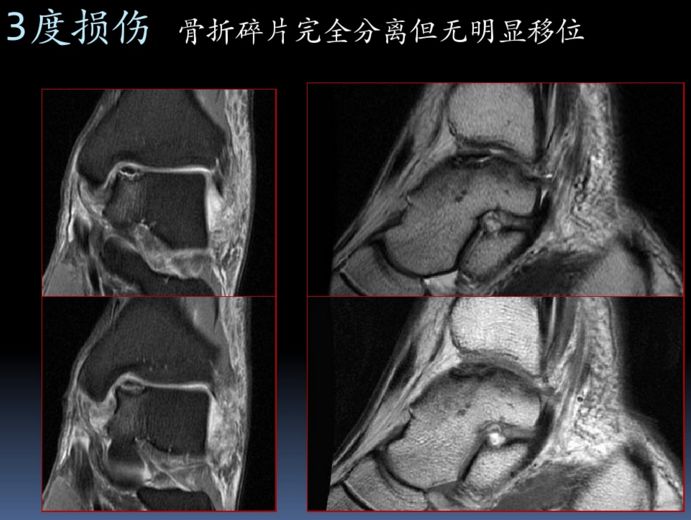

三角韧带损伤(一)